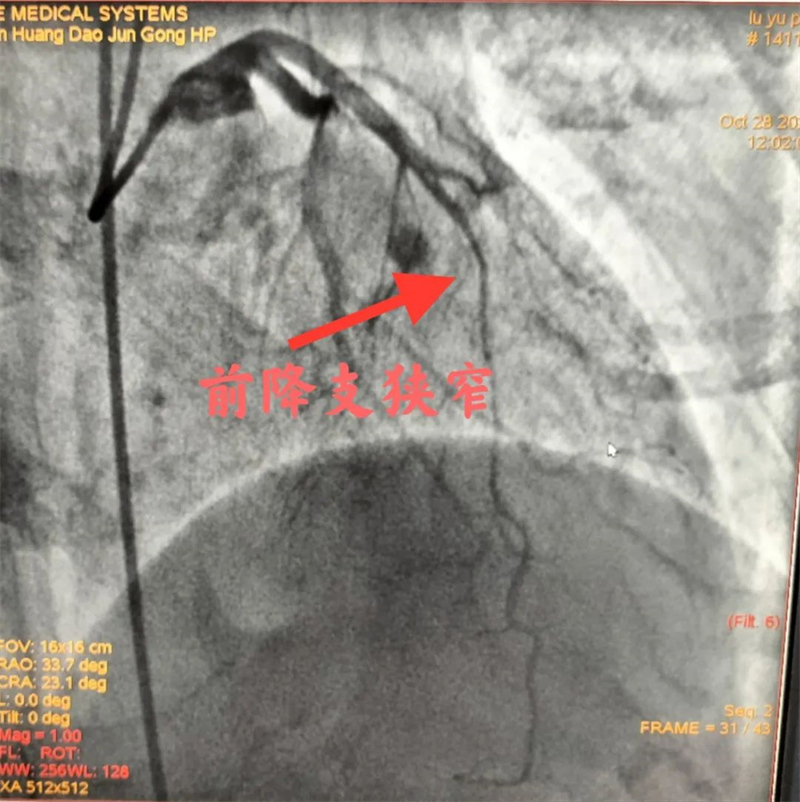

经过充分的准备后,心血管内二科及神经血管介入科团队通过股动脉穿刺,为患者顺利完成冠状动脉造影、肾动脉造影及左侧锁骨下动脉造影。冠状动脉造影结果提示患者前降支远段70%狭窄,确诊为冠状动脉粥样硬化性心脏病。肾动脉造影提示左侧肾动脉起始段中度狭窄,明确了肾动脉狭窄。左侧锁骨下动脉造影提示起始段次全闭塞。成功植入两枚支架,术后患者头晕缓解,左侧桡动脉搏动有力。